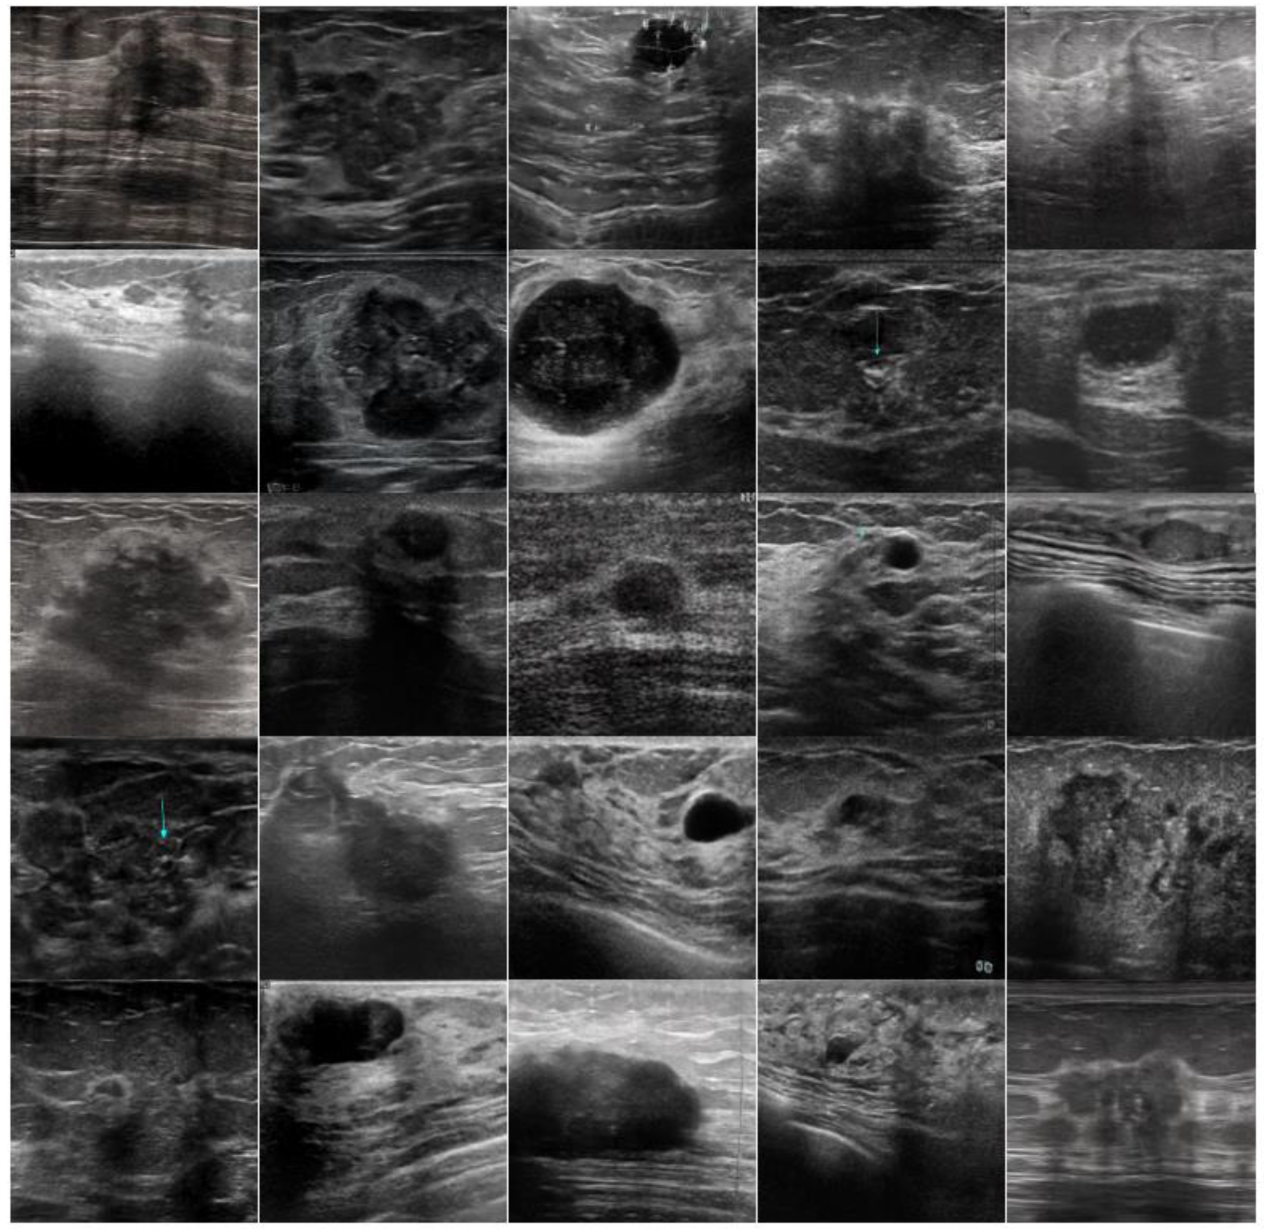

To enhance the quality and diversity of the training dataset, generative adversarial network technology (StyleGAN3) [44] was employed, configured to create ultrasound images of breast lesions. A crucial aspect of the generation process was the production of images with a resolution of 512 × 512 pixels. This size was chosen to preserve the high image detail and quality, which is critically important for ensuring the accuracy of the subsequent classification. The model was trained separately for each class of lesion, which allowed for the generation of category-specific images while maintaining their high resolution. The training process of the StyleGAN3 model continued until kimg = 1000 was reached, which provided a sufficient degree of training for generating high-quality 512 × 512 images. This resolution was strictly maintained throughout the entire generation process to ensure that all the generated images would have consistent sizes and the quality required for accurate and efficient classification.

(Explanation: kimg = 1000 means that the training process will continue until the model has seen 1,000,000 (1000 thousand) real images in total. The quality of the generated images was assessed using the Fréchet inception distance (FID) metric, which quantitatively measured the closeness of the distribution of the generated images to the original dataset. It is reported that the FID metric reached 22.9 for malignant lesions and 35.4 for benign lesions, indicating the high quality and realism of the images generated at a resolution of 512 × 512).

Following the completion of training of the StyleGAN3 model and achieving FID values of 22.9 for malignant lesions and 35.4 for benign lesions, a detailed visualization of the results was conducted to assess the quality of generation. For each class, 25 generated images were selected and visualized in a tile format, allowing for a clear evaluation of the diversity and realism of the synthetic images (Figure 5). This visualization serves as further confirmation of the effectiveness of using generative adversarial networks to enhance training datasets in medical diagnostics.